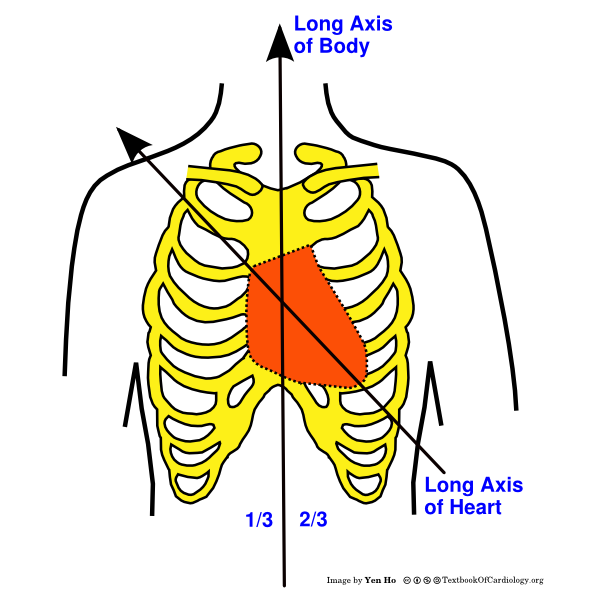

Cardiac magnetic resonance imaging (MRI) is used for visualizing the heart and evaluating various types of heart diseases like cardiomyopathy, ischemic heart disease, valvular defects and pericardial defects. Typically, what happens in the CMR protocol is the patient is passed through a huge barrel-shaped scanning machine and on the other side, technicians acquire images of the heart.

Delving a bit deeper into the imaging protocol, the first step is to acquire images in the standard anatomical views – which are the sagittal, transverse and coronal views, shown below.

This a step-by-step protocol outlined in detail in cardiac MRI textbooks. Basically, the radiographer takes an initial heart image (preferably an image of the standard transverse view) and then prescribes lines on it. Using these lines as a guide, the MRI machine, “slices” the image to create the subsequent image view.

There are many possible views that can be constructed in the CMR protocol, however two imaging views are mandatory for the radiographer to capture – these are the four-chamber (4Ch) view and the two-chamber (2Ch) views. They are named so because they visualize the different chambers of the heart.

In a 4Ch view, all 4 chambers of the heart are visible and in the 2Ch view, only two are visible. To create the 4Ch view, the radiographer first prescribes a line on the transverse image, and then on the 4Ch view image, he/she prescribes another line passing through the left side of the heart (through the mitral valve and ventricular apex), slicing the image to create the 2Ch view. The workflow below shows the 4Ch view on the left and how a line is drawn (shown in yellow) to slice the image and create the 2Ch view on the right.